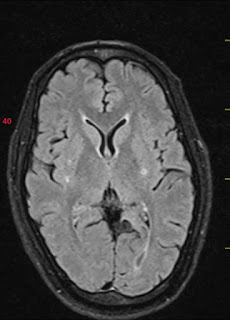

27 yr old male presented to casuality with c/o giddiness 6hrs ago ,

Right UL and LL weakness since 6 hrs

Deviation Of angle of Mouth to left

Slurring of speech since 6 hrs

Patient is apparently asymptomatic 6hours ago while he was driving Tractor hehad 2 episodes of Giddiness following that he developed Right Upper And Lower Limb weakness, sudden in Onset ,Non Progressive,Unable to lift the hand Above the level of head. Deviation Of angle of mouth to Left side

BP:- 200/140 mmHg